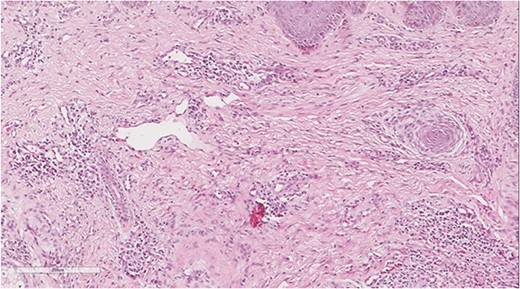

A 5 mm skin punch biopsy was also taken from the neck. Histopathology showed cystically dilated hair follicle with surrounding fibrosis and heavy inflammatory infiltrate and granulation tissue (Fig. 1), the inflammatory infiltrate is composed of lymphocytes, plasma cells, neutrophils and histiocytes (Fig. 2). The overall morphologic picture was suggestive of follicular occlusion syndrome (Fig. 3). A diagnosis of HS was made, and the patient was started on rifampin 600 mg OD and clindamycin 300 mg BID. A lipid panel was ordered as well and showed a triglyceride level of 1.99 mmol/L (0.7–1.7 mmol/L).

Dilated hair follicle with perifollicular inflammation and adjacent foreign body giant cell reaction secondary to ruptured dilated hair follicle in a background of dermal fibrosis.

Perivascular lymphoplasmacytic infiltrate that is a common finding in HS.